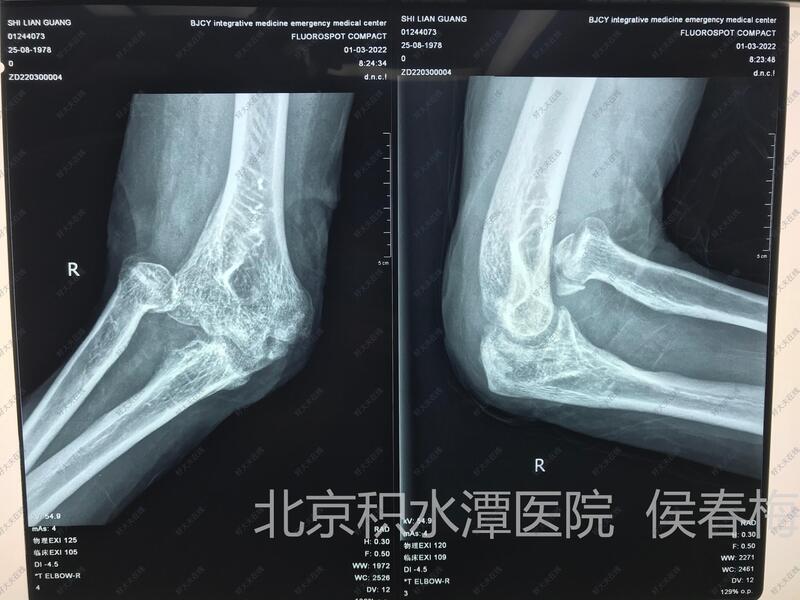

治疗前

患者1年前车祸造成多发损伤,目前右桡骨小头脱位,前臂旋转受限,腕关节背侧瘢痕挛缩,腕关节僵在背伸位,手指伸直受限。